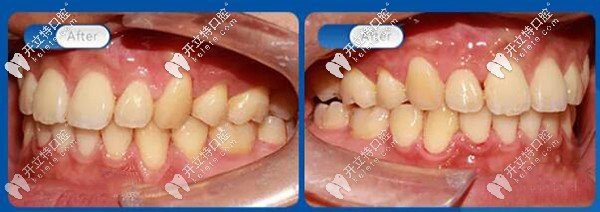

45度看,解除牙列擁擠,解除牙弓前凸,解除磨牙深覆蓋,恢復(fù)正常咬合關(guān)系。

解除牙弓前凸